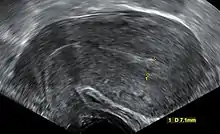

Transvaginal ultrasonography after an episode of heavy bleeding in an intrauterine pregnancy that had been confirmed by a previous ultrasononography. There is some widening between the uterine walls, but no sign of any gestational sac, thus in this case being diagnostic of a complete miscarriage.

A complete miscarriage is when all products of conception have been expelled; these may include the trophoblast, chorionic villi, gestational sac, yolk sac, and fetal pole (embryo); or later in pregnancy the fetus, umbilical cord, placenta, amniotic fluid, and amniotic membrane. The presence of a pregnancy test that is still positive as well as an empty uterus upon transvaginal ultrasonography does, however, fulfill the definition of pregnancy of unknown location. Therefore, there may be a need for follow-up pregnancy tests to ensure that there is no remaining pregnancy, including an ectopic pregnancy.